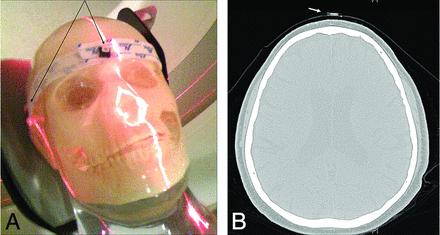

Doses were measured with optically stimulated luminescence dosimeters at 4 locations with respect to the surface of the patient's head. The same measurements were performed on the acrylic skull phantom (Fig 1A). The optical stimulated luminescence dosimeters used were 1 cm × 1 cm aluminum oxide–based nanoDots19 (Landauer, Glenwood, Illinois) and were read by using a microStar reader (Landauer). The microStar reader was calibrated according to manufacturer's user manual recommendations by using 5 control nanoDots provided with the dosimetry system. The dosimeters were tested for reproducibility with 5 exposure measurements in air at 120 kVp. They demonstrated very good reproducibility (coefficient of variation, 0.01).

A, Acrylic skull phantom with nanoDots at forehead and lateral locations. B, Patient CT image with nanoDot on forehead.

Two nanoDots were placed on the surface of the patient's head: 1 on the forehead (Fig 1B) and 1 on the back of the head. Two nanoDots were also placed at locations on the head holder adjacent to the left and right temporal bone. At these lateral locations, the dosimeters were placed on the head holder instead of the patient's head to avoid disturbing the patient. Each individual patient's PSD was specified as the maximum of the 4 measurements.

Doses were measured with optical stimulated luminescence dosimeters at the same 4 locations on the surface of the acrylic skull phantom (Fig 1A) during 2 separate trials by using an interventional x-ray fluoroscopy imaging system (Innova 3100; GE Healthcare, Milwaukee, Wisconsin) with examination technique factors typically used during neurointerventional imaging, producing a total of 8 dose measurements. The maximum dose to the phantom for each assessment was specified as the PSD of the 4 measurements. The total cumulative air kerma (CAK) was also recorded from the imaging system display for each trial. This is specified as the CAK at the interventional reference point.20 The PSD to CAK ratio was calculated for each assessment.21